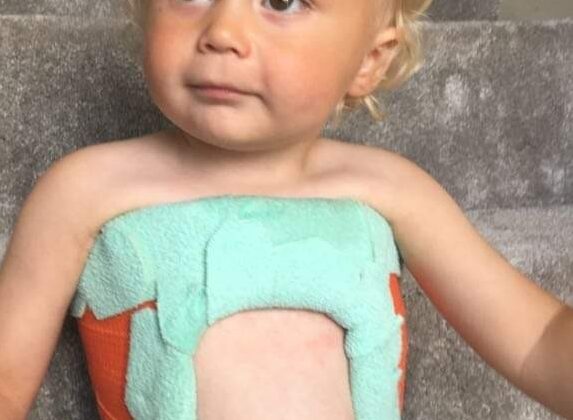

التجبير التسلسلي يُمثل علاجًا غير جراحيًا يعتمد على جبائر خاصة يضعها الطبيب حول جذع الطفل. وتعمل هذه الجبائر على تثبيت العمود الفقري في وضعية أكثر استقامة. ومع مرور الوقت، يقوم الطبيب بتغيير الجبيرة وتعديلها بشكل متكرر لتصحيح الانحناء تدريجيًا.

يضع الطبيب الجبيرة تحت التخدير لراحة الطفل وضمان الدقة.

يمدد العمود الفقري ويعيد توجيهه، ثم يشكّل الجبيرة لتثبيت الوضعية الجديدة.

يغير الجبيرة كل عدة أشهر تبعًا لاستجابة العمود الفقري ونمو الطفل.

بما أن عظام الأطفال في السنوات الأولى لا تزال مرنة وقابلة للتصحيح، فإن التجبير التسلسلي يعطي أفضل النتائج خاصةً قبل سن الثالثة.

يختار الفريق الطبي مواد آمنة لضمان راحة الطفل، مثل:

الألياف الزجاجية: خفيفة ومرنة لكنها قوية.

الأربطة: تساعد على تثبيت الجبيرة بشكل محكم مع إمكانية التعديل.

بطانات جلدية: تحمي الجلد من التهيج والاحتكاك.

هذه المواد تجعل ارتداء الجبيرة أسهل، وتقلل من المضاعفات الجلدية المحتملة.